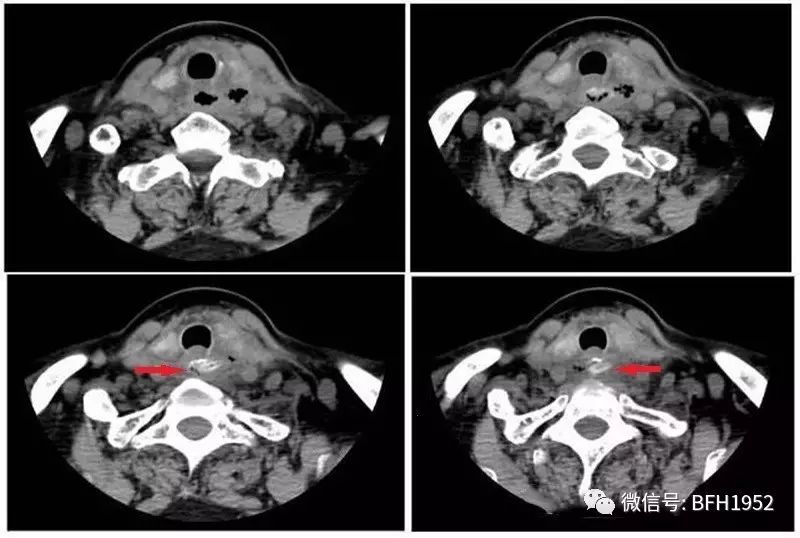

无独有偶,时隔半天,大年初五的晚上十点钟,耳鼻咽喉头颈外科急诊又来了一位食道异物的患者,患者是一位68岁的老人,三天前她在进食红枣时不慎误咽,但是没有重视,近三天她虽有咽痛及吞咽困难的症状但是仍然未间断进食。在就诊前12小时,她出现了发热,体温最高达到了39.3℃。来到友谊医院后经诊断为食道异物、食道穿孔,且穿孔周围有脓肿形成,考虑到患者出现发热及血象增高,是典型的感染症状,如果不及时清创引流很可能出现颈部脓肿进一步加重,感染中毒性休克等并发症危及生命。

北京友谊医院耳鼻咽喉头颈外科主任医师刘良发当机立断,决定在急诊施行全麻颈侧切开颈部脓肿清创引流术、食道异物取出及食道修补术。术中可见整颗枣核卡在食道入口处,枣核尖端露出,造成了约0.5*0.5cm大小破损。经过手术治疗目前患者体征平稳,恢复良好。

图2 第二例食道异物患者颈部CT平扫,轴位软组织窗可见食道入口处横行枣核样异物,食管周围组织肿胀,可见气体密度影,左侧甲状腺背叶近左侧颈鞘周围为著,不排除脓肿形成